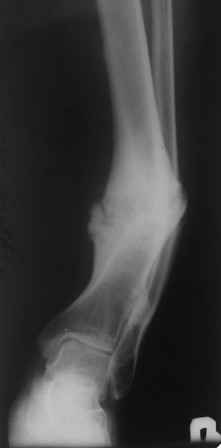

Несращение голени с наличием деформации. |

Больной 33г, лечится в течение 2-х лет, выходил на работу. Первоначально, был выполнен остеосинтез двумя шурупами с дополнительной фиксацией перелома наружной гипсовой повязкой. Снята преждевременно в поликлинике, через 3 месяца после операции, постепенно возникла варусно-рекурвационная деформация.Больному был наложен АВФ, с постепенной устранением деформации. Демонтаж АВФ через 4 месяца. Спустя 3 месяца появилась болезненность и стала нарастать деформация. В настояще время больной ходит с тростью, с полной нагрузкой на конечность. Имеется варусно-рекурвационная деформация 45-20 градусов. Болезненность при пальпации, незначительная подвижность в зоне перелома. Взгляды коллег разошлись: 1. Наложить АВФ с остеотомией м/б кости, постепенное исправление деформации, после, БИОС. 2.Наложение АВФ с остеотомией в зоне ложного сустава, коррекция деформации- постепенная, после исправления осей- БИОС. 3.Открытая репозиция перелома, одномоментное устранение деформации, БИОС.